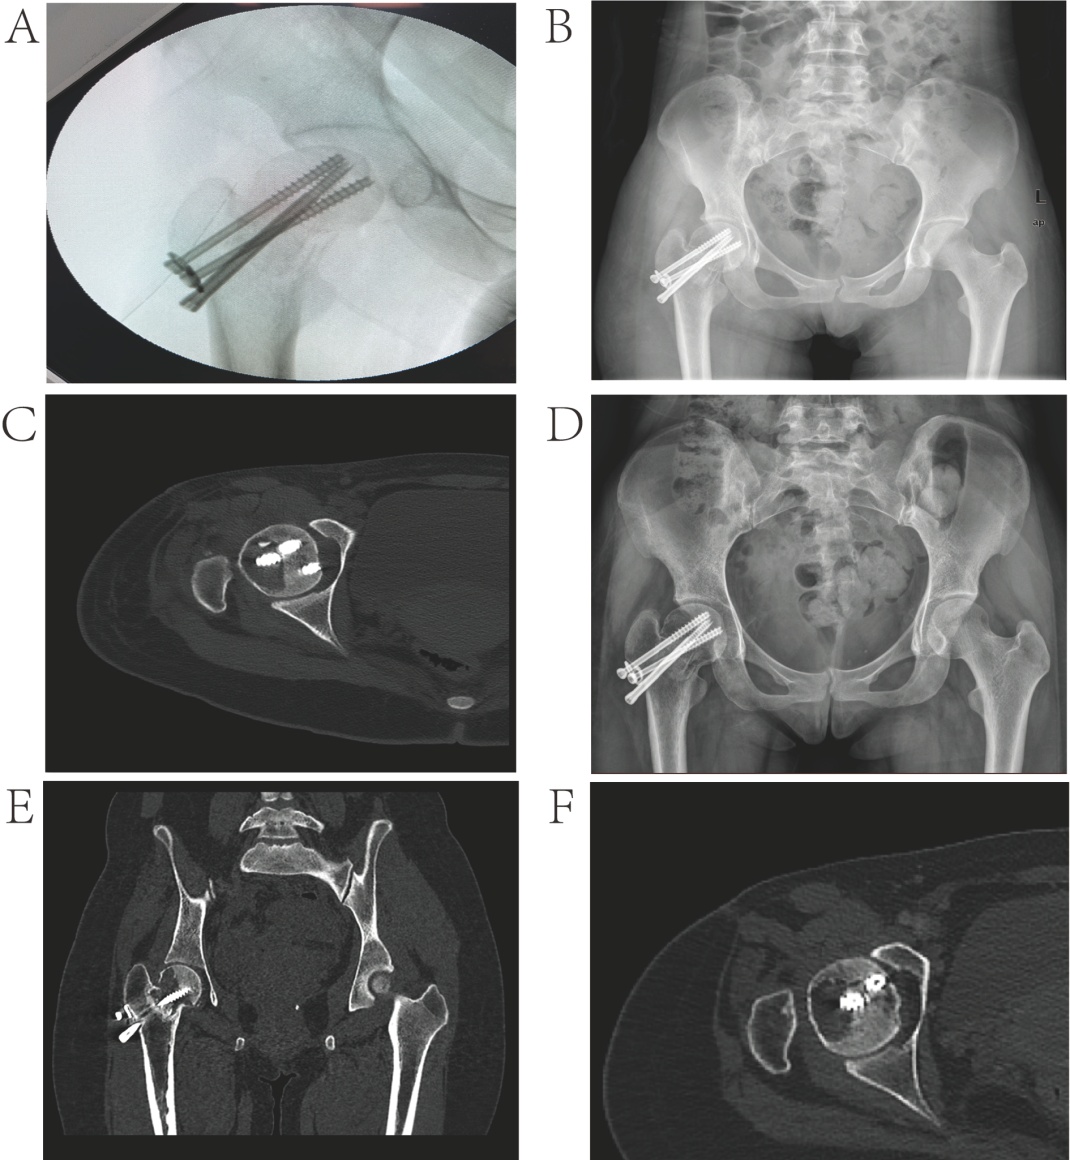

(A)~(F) 展示了患者的术后系列影像图片。(A) 术中C型臂透视显示三枚空心螺钉的置入。(B) (C) 术后1周评估:X线片显示螺钉位置良好;轴位CT显示残留囊腔持续存在。(D) 术后4周影像:X线片。(E) 术后32周CT显示部分骨痂形成及囊腔缩小。(F) 术后48周最终随访:CT确认骨折不愈合。

术后康复方案包括使用双拐辅助行走、为期3个月的非负重期,并辅以循序渐进的床上被动至主动肌肉强化练习。按计划在术后3~4个月进行随访,包括髋关节X线摄影和CT扫描。术后32周的影像学评估显示皮质连续性部分恢复,残余空腔体积减小,股骨头内信号强度稳定,无复发迹象。至48周时,观察到持续的不愈合(见图3),基于肌肉骨骼肿瘤协会评分为15分以及患者的意愿,考虑进行全髋关节置换术。上述手术旨在维持生活质量并适应未来可能的妊娠。在术后1年随访时,患者功能恢复满意,MSTS评分为27分,已恢复日常活动,并且没有肿瘤复发的迹象。

入院一周后,患者通过外侧入路接受了病灶清创术。术中可见股骨颈部及头部软组织呈易碎、红白色、棉絮样质地(见图2(A)),将其完全刮除,随后进行骨面打磨。冰冻切片分析显示散在的单核间质细胞中穿插着破骨细胞样多核巨细胞和局灶性梭形细胞,伴有轻度细胞学异型性。鉴别诊断包括动脉瘤样骨囊肿、富含巨细胞的骨肿瘤和骨肉瘤。在最大限度保留软骨的根治性刮除术后,用过氧化氢和聚维酮碘大量冲洗空腔。通过内旋和内收患肢实现骨折复位,同时使用三枚从股骨外侧皮质插入股骨头的空心螺钉进行固定。使用同种异体骨移植结合骨水泥增强来重建缺损。术中透视验证了螺钉位置满意(见图3(A)),然后分层关闭伤口。